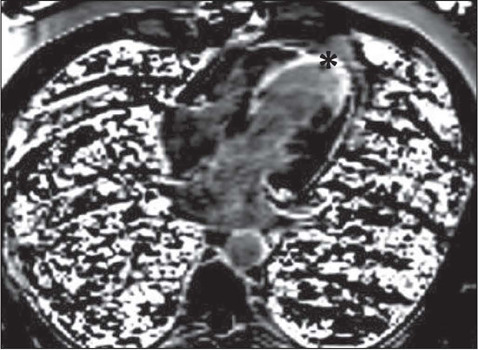

Results: Pathological results were seen in six (30%) of the patients in our study sample. Scar tissue was identified as a high-risk factor in three patients (15%), and myocardial hibernation was shown to pose a moderate risk in three patients (15%). In the remaining 14 cases, no pathology was identified, and the risk was therefore categorized as low. A statistically significant disparity in mortality rates was observed between the high- and low-risk groups (p < 0.05). There were no statistically significant differences between the two groups in terms of the ECG and cardiac biomarkers.

Conclusion: Our findings indicate that CMRI is effective in accurately categorizing risk groups and detecting ischemic conditions, even when such events are not evident on ECG or laboratory tests.

Abstract Image